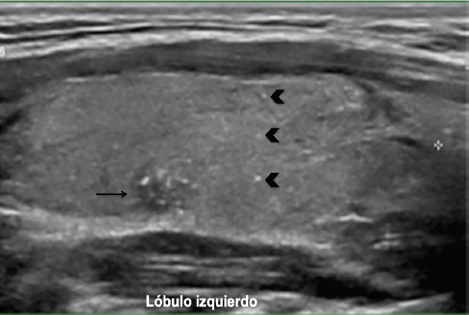

En el US de cuello la glándula tiroides es de situación normal y sus bordes son regulares y bien definidos, el lóbulo derecho tiene medidas de 16 × 13 × 41 mm en sus ejes anteroposterior, transversal y longitudinal respectivamente, el lóbulo izquierdo mide 16 × 16 × 47 mm en los mismos ejes, con un volumen tiroideo total de 10.6 ml, en el parénquima tiroideo del lóbulo izquierdo se identifica una imagen nodular sólida, hipoecoica (figura 2), más ancha que alta, de bordes mal definidos y sin extensión extratiroidea, con múltiples ecos puntiformes en su interior y con diámetro máximo de 6 mm, el cual se clasifica como TI-RADS 5 según los criterios del Colegio Americano de Radiología (ACR)5. También se identificaron múltiples ecos puntiformes de distribución difusa en ambos lóbulos tiroideos (figura 3), el resto del parénquima se observa sin alteraciones.

Figura 2 Nódulo tiroideo de 6 mm en el borde posterior del lóbulo izquierdo TI-RADS ٥ (flecha). Además, se observan ecos puntiformes en el parénquima (cabezas de flecha).